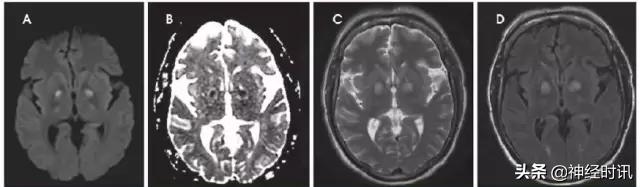

常染色体显性遗传性脑动脉病伴皮层下梗死和脑白质病(CADASIL)是一种可累及脑穿通动脉和软脑膜动脉平滑肌的遗传性疾病。患者的通常表现为:在30或40多岁时,开始出现偏头痛、TIA和缺血性卒中的症状,并在其后的几十年里逐渐发展为痴呆。其MRI检查多显示为幕上白质的融合性、斑片状T2高信号及深部灰质、中脑和脑桥部位的腔隙性梗死。CADASIL的主要特点是双侧前颞叶白质和外囊受累,且急性病变多表现为弥散受限(图16)。

图16 一例40岁的男性患者,因意志力缺乏和左侧面部下垂而急诊就医。MRI显示其双侧半卵圆中心和放射冠部位有多灶性的弥散受限和增强改变(A:DWI,B:ADC),并伴有双侧脑室周围白质、双侧前颞叶部位相关的T2高信号病灶(C&D:T2WI)。Notch 3基因突变证实了其为CADASIL。